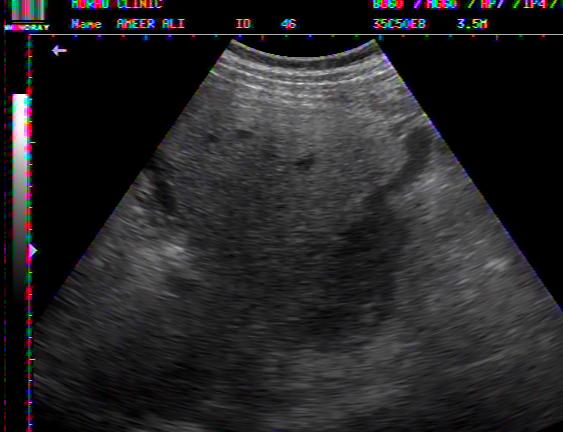

PELVIC ASCITES IN DHF